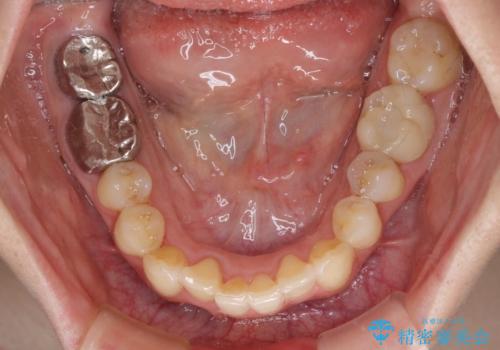

- 前歯のデコボコと奥歯の虫歯を気にして来院された患者様です。

主に下顎歯列全体の後方移動とIPR(歯と歯の間を削る)によってデコボコが解消するように設計し、インビザラインにより治療を行うこととしました。

矯正治療後半に下顎左右奥歯をセラミッククラウンにて補綴し、その後インビザラインによる歯列の仕上げを行うこととしました。

下顎前歯の叢生が速やかに改善されたため、1年3か月で治療を終えることができました。

下顎前歯は後戻りを起こしやすいため、舌側を細いワイヤーで固定することで後戻り対策を行っています。